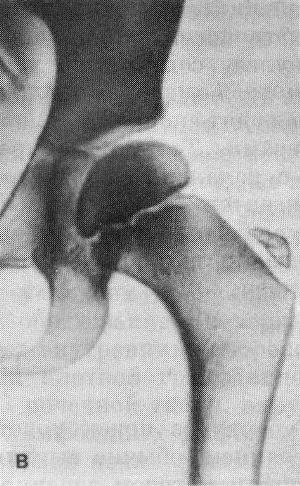

Особенно подвержены поражению кости, которые хорошо снабжаются кровью. Это плечевая кость, бедренная кость, позвоночник, голень и предплечья.

Костный туберкулёз легко обнаруживается при рентгенологическом исследовании костей. При этом можно обнаружить все очаги разрушения костной ткани, секвестры и даже абсцессы. Для диагностики очень важно получить кусочек отмершей кости. Это необходимо для того, чтобы определить в ней наличие микобактерий.